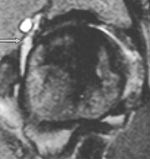

Degenerativ labrum viste økt signalintensitet i labrum uten affeksjon av overflaten med inntakt recess hos to pasienter (fig 3) og med manglende fremstilling av recess hos tre pasienter (fig 4). Sistnevnte ansees forårsaket av labrumhypertrofi. Labrumruptur ble diagnosisert hos ti pasienter. Ruptur ble beskrevet når man kunne identifisere kontrast mellom labrum og acetabulum (fig 5) eller imbibering av kontrast i labrum (fig 6). Alle rupturene satt i øvre del av labrum.To av disse pasientene er operert, og vårt funn ble verifisert. Begge var aktive fotballspillere, og de hadde henholdvis stadium 2B og stadium 3B ved MR-artrografi. Dette samsvarte med de artroskopiske funn. Den tredje pasienten som er operert, viste forandringer forenlig med villonodulær synovitt. Også dette ble verifisert ved artroskopi (fig 7).

Vi brukte Czerny og medarbeideres klassifikasjon av labrumskader ved MR-artrografi (2). Stadium 0 er normal labrum. Stadium 1 viser økt intralabral signalintensitet, forenlig med degenerativ labrum. Stadium 2 viser imbibering av kontrast inn i labrum, forenlig med ruptur. Stadium 3 viser kontrast mellom labrum og acetabularbrusken, forenlig med avrivning av labrum fra acetabulum. Ved bevart recess i stadium 1 – 3 brukes A i tillegg, mens det ved manglende fremstilling av sulcus brukes bokstaven B. Stadium B tilsier at labrum er hypertrofiert. I praksis betyr det at stadium 2 og stadium 3 viser patologiske forandringer i labrum som vil kunne behandles med ortopedisk intervensjon.